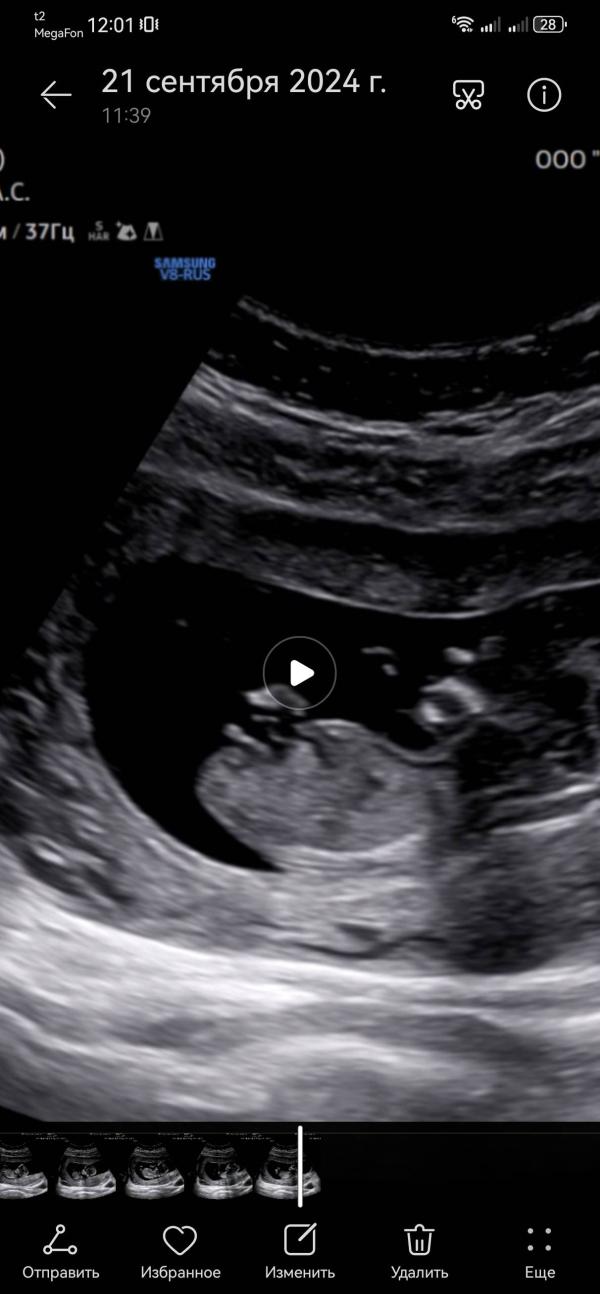

Самые зоркие, самые опытные, открываем гадание по половому бугорку 😄😊

Это один и тот же ребёнок и одно и то же видео

А мне кажется девочка, для мальчика как будто угол бугорка не такой острый

@belayar, по углу вот этого бугорочка 😅 у девчонок с нашим сроком умудрялась угадывать

А мне кажется девочка, просто пуповина так торчит